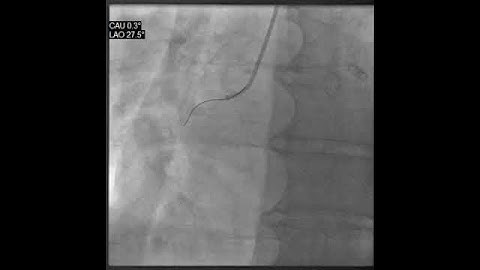

Room C- C2- Managing Guidewire and Device Entrapment in PCI